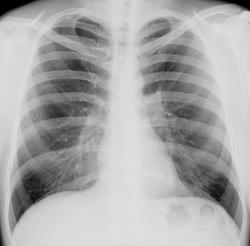

Мужчина 1981 года рождения. Жалоб нет. Проходил пофосмотр в поликлинеике. Когда проходил флюорографию сказал лаботанту: "...у меня киста там где-то была..." и убёг. Не успел я его поймать сразу, да боком поставить)), но можт поймаю еще.

Да,справа в S6 округлой формы кистозная полость-врожденная патология.

Почему то снимок не увеличивается. Кольцевидная тень в среднем отделе правого легкого,тонкостенная полость, без бокового принадлежность к сегменту сказать нельзя.

Бок доснял снимок пока выложить не могу, но на словах: булла(киста?) в S3. Выглядит точно ткаже как и на прямом снимке. Прилежит к передней грудной стенке.

Со слов пациента - перенес пневмоторакс...хирург при выписке сказал: "...расслабься, а то взорвется..."

Со слов пациента - перенес пневмоторакс. Уплотнение апикальной плевры вполне может быть как остаточные изменения после него. Нет?